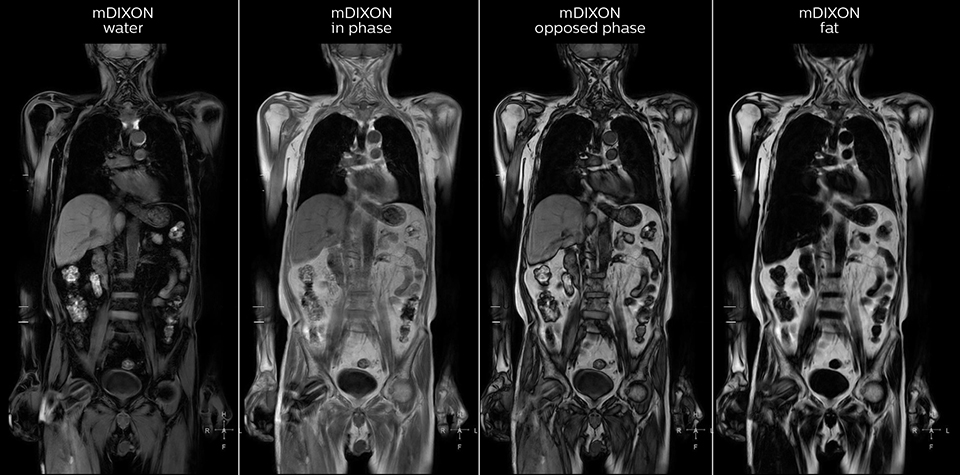

“mDIXON FFE allows us to quickly get information we need to assess the presence of fat. That gives us more information when we need to diagnose bone lesions, and when we are asked to judge fat-containing lesions such as hepatocellular or renal carcinoma,” Dr. Nobusawa says. “The mDIXON fat images can help us to differentiate fatty bone marrow from bone lesions. This is especially useful in elderly people, who tend to have fattier bone marrow. The water images provide a high signal-to-noise ratio in the intestinal canal, which is valuable for visualizing lesions in the colon,” he says.

Kawasaki Sawai Hospital’s whole body protocol also includes an mDIXON FFE sequence. Because mDIXON provides images for four contrast types – water only, fat only, in-phase and out-of-phase – from a single acquisition, it is useful in many ways.

“In-phase and out-phase sagittal T1-weighted FFE images help us to visualize and further characterize bone lesions such as metastasis and bone-marrow hyperplasia that have high signal on DWI. These images are also used throughout radiotherapy, to monitor changes in the fatty bone marrow.”

“When we limited the scan coverage to the area from neck to femur, we could fit more clinical information in approximately the same scan time. So, we added coronal mDIXON, sagittal T1-weighted, and sagittal STIR sequences to our examination, instead of performing only axial DWIBS and coronal single-shot TSE scans.” The single shot T2-weighted TSE images are used for morphology and compared to DWIBS images to identify T2 shine-through. Sagittal STIR images are used in patients with inflammation or bone metastasis.